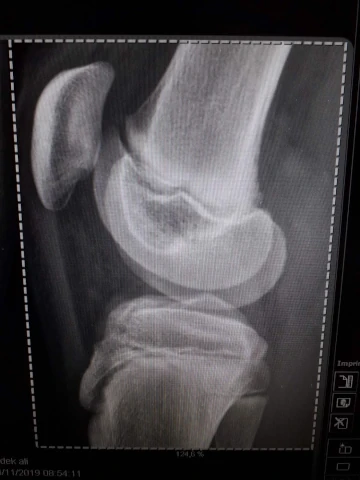

Fracture épaule

img